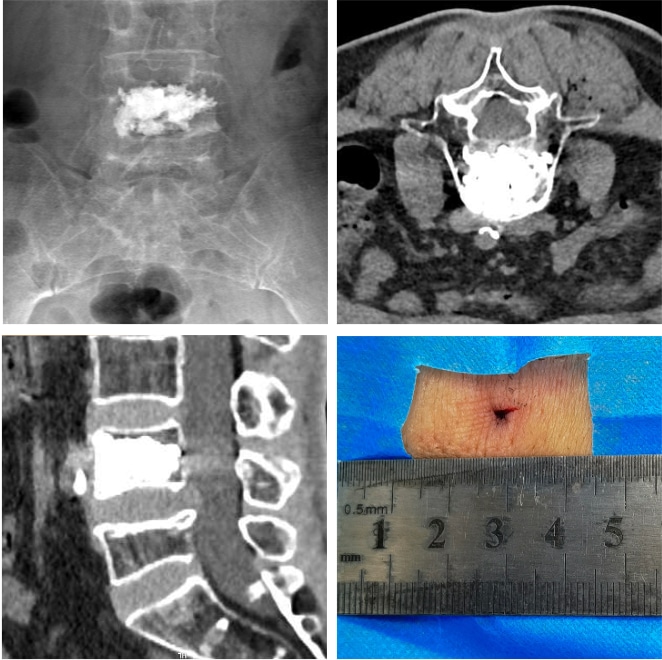

55岁的李女士,既往肺癌病史,一个月前出现腰背痛,无法下床活动。经过详细查体和阅片后,明确诊断为:脊柱恶性肿瘤(肺癌转移)。考虑其全身状况较差,无法耐受开放手术,吴敏飞教授决定采用单针微创精准消融技术为患者治疗。

▲术前核磁:腰4椎体骨质破坏,病理性骨折

▲术中情况:CT引导下精准穿刺至病灶区域

手术结束后,李女士腰痛症状即刻得到缓解,面带微笑步行走出手术室。术后影像学复查,肿瘤消融彻底,切口小于三毫米。

▲术后效果:立即下地活动 ▲复查影像学与手术切口(<3mm)